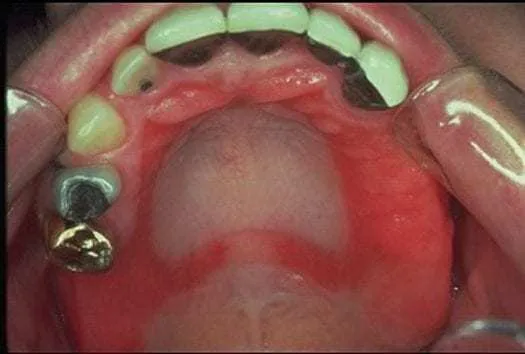

- Zaczerwienienie i rumień: Błona śluzowa jamy ustnej może stać się wyraźnie zaczerwieniona, czasem z widocznym obrzękiem. Zmiany te mogą być zlokalizowane lub obejmować większe obszary.

Kontaktowe zapalenie błony śluzowej jamy ustnej, znane również jako stomatitis contacta, to stan zapalny wywołany bezpośrednim kontaktem błony śluzowej z substancją uczulającą lub drażniącą. W kontekście alergii na nikiel, jest to właśnie jedna z głównych form, w jakiej objawia się reakcja alergiczna. Nikiel, uwalniając się z materiałów stomatologicznych, działa jako alergen, prowadząc do miejscowego stanu zapalnego błony śluzowej jamy ustnej.